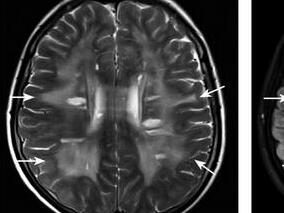

1小时条评论1 病例简介 患者女,23岁。因言语不清伴右侧肢体无力10个月,视力下降8个月,头痛2个月于2006年10月27日入院。患者2005年12月下旬突然出现右侧肢体无力,在当地医院就诊,因患者发病3周前有咳嗽、头痛、乏力及发热,体温最高达38.9℃,发病2周前出现口周疱疹,并不...

1小时条评论1 病例简介 患儿女,7岁,因反复发作性抽搐9个月,左侧肢体乏力6个月于2007年11月17日入院。患儿于9个月前无明显诱因下被发现突发双眼向左凝视,嘴角向右抽动,伴傻笑,对周围事物无反应,约20秒后自行缓解,之后间断出现3次类似症状。约6个月前,家人发现患儿行走...